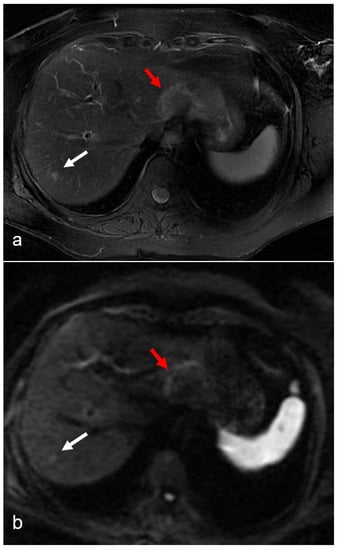

Shin et al. [36] reported that the presence of hepatic reticular hypointensity in the hepatobiliary (HB) phase of gadoxetic acid-enhanced MRI was highly specific for the diagnosis of SOS (Figure 3).

Figure 3.

(a–d) A 55-year-old man with hepatic metastases from rectal cancer undergoing neo-adjuvant chemotherapy with folinic acid, 5-fluorouracil, and oxaliplatin (FOLFOX). After chemotherapy, in the same plane as metastasis of the left lobe (red arrow), a small focal lesion developed in segment 6 (white arrow). The lesion was hyperintense in the T2-weighted image (a) and presented a slight restriction in the DW-MRI image, with b-values of 1000 s/mm2 (b). The arterial phase (c) of the Gd-EOB-DTPA-enhanced MR image demonstrated homogeneous and strong enhancement at the level of the lesion, which presented a doughnut-like enhancement with hyperintense periphery and a hypointense center in the hepatobiliary phase image (d). The findings are consistent with an FNH-like lesion. In the hepatobiliary phase image (d), the patchy heterogeneity of the surrounding hepatic parenchyma, with reticular enhancement and scattering of hypodense areas, is also appreciably suggestive of SOS.